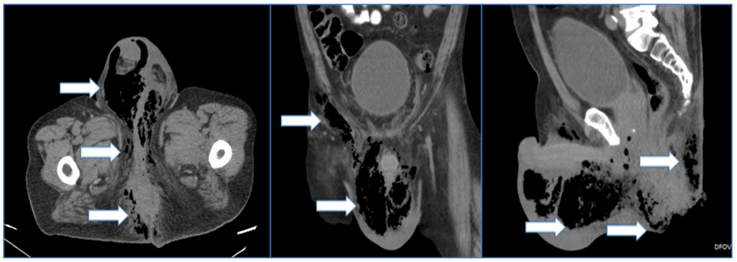

La tomografía computarizada es considerada actualmente la principal herramienta imagenológica 26; es útil cuando se sospecha compromiso de los tejidos profundos o del espacio retroperitoneal. Es específica para determinar la extensión de la enfermedad, etiología subyacente, engrosamiento de los planos faciales con presencia de gas e infiltración de la grasa (figuras 2 y 3) 32,53. También sirve para evaluar las vías anatómicas de diseminación y la presencia de colecciones líquidas o abscesos, incluyendo las extensiones retroperitoneal, intraabdominal o torácica 54.

Figura 2. Tomografía computarizada que muestra el proceso inflamatorio enfisematoso que afecta la región perianal, genital, glútea e inguinal derecha. Se observa proceso enfisematoso a nivel de la grasa peri-rectal. Las flechas blancas señalan las áreas de enfisema.